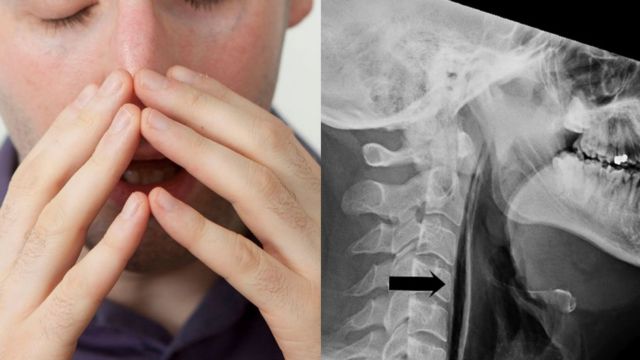

Όταν τον εξέτασαν οι γιατροί διαπίστωσαν ότι υπήρχε οίδημα στον λάρυγγα και γύρω από τον λαιμό του. Ακτινογραφία αποκάλυψε ότι αέρας εξερχόταν από την τραχεία του προς τον μαλακό ιστό του μέσω της “ρωγμής” που είχε σχηματιστεί.